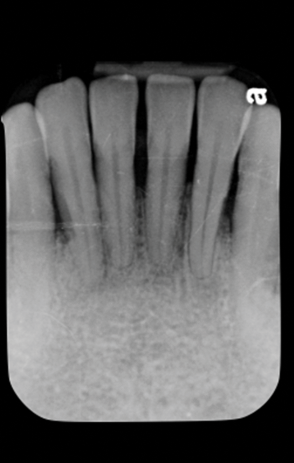

Fig 4. Case 1. Initial presentation of a patient with periodontitis (teeth Nos. 22 through 27). Generalized pocket depths of 5 mm to 6 mm were present.

Figure 4

Fig 5. Initial radiograph of the Case 1 patient, teeth Nos. 22 through 27.

Figure 5

Fig 7. Case 2. Initial presentation of a patient with periodontitis (teeth Nos. 22 through 27). Generalized pocket depths of 6 mm to 7 mm were present, with wire splint on teeth Nos. 23 through 25.

Figure 7

Fig 8. Initial radiograph of the Case 2 patient, teeth Nos. 22 through 27. Fig 9. SRP resulted in the elimination of inflammation and remaining probing depths of 2 mm to 3 mm in Case 2 patient, 3 months post-therapy. (Fig 4 through Fig 9 are courtesy of Dennis Tarnow, DDS.)

Figure 8

Numerous publications emphasize that oral hygiene and SRP to remove bacterial biofilms and calculus are essential facets of nonsurgical periodontal therapy.39-42 Subsequent to treatment, clinical signs of gingival inflammation (eg, redness), BOP, and probing depths are significantly reduced around single- and multi-rooted teeth (Figure 4 through Figure 9).41,42 A direct relationship has been reported between changes in clinical attachment level (CAL) and probing depth compared to initial pocket depth. The greatest gain of CAL and probing depth reduction occurs at locations with deep pockets (≥7 mm).40-42 The following clinical effects were noted after SRP: mean probing depth reductions at shallow pockets (1 mm to 3 mm), moderate sites (4 mm to 6 mm), and deep sites (>7 mm) were, respectively, 0.03 mm, 1.29 mm, and 2.16 mm.40 The average alterations in CAL for shallow, moderate, and deep probing sites were -0.34 mm (loss of CAL), 0.55 mm, and 1.19 mm, respectively (gain of CAL in the latter two groups).40 Root planing causes CAL loss at shallow probing sites (1 mm to 3 mm),40,42 because it removes cementum where Sharpey's fibers insert into the tooth.43 Proye et al showed recession may occur 1 week after root planing while a gain of CAL is seen in 3 weeks.44 These data indicate that patient alterations in probing depth and CAL may be reassessed 3 to 4 weeks after root instrumentation.